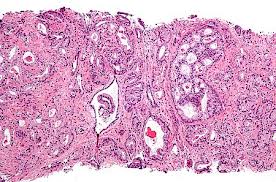

Рак простаты в семье – повод обратиться к урологу мужчинам старше 20 лет

Наличие семейной предрасположенности требует начать поиск признаков злокачественного роста уже после 20 лет. К такому выводу пришли исследователи из Университета Луизианы (США).

По мнению руководителя группы исследователей, профессора Пэтти Эндрю, необходимо учитывать, что рак принимает новые формы, часто протекает бессимптомно до запущенных стадий. По ее мнению, задача ранней диагностики состоит в том, чтобы определить начало развития рака за шесть и более месяцев до появления первых клинических симптомов болезни. Если установлен рак предстательной железы на ранней стадии, у специалистов появляется выбор, как лечить, применить ли гормональную терапию, радиационную или хирургическое пособие, а также возможность использовать наиболее щадящую технику, уменьшить влияние последствий операции на образ жизни пациента.